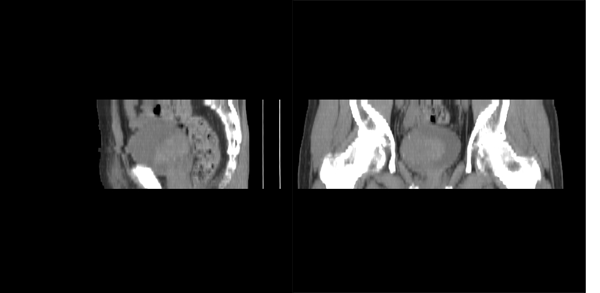

m79y自述30年前做过疝手术,20年前间断出现尿血,每次经抗炎治疗后即好转,近一月来又出现尿血但抗炎后仍尿血.现做双肾+盆腔ct:

盆腔5mmct扫描

该病人年龄过大故放弃了增强.ct做完后本人检查病人发现病人耻骨联合上稍偏右见一突出的包块影,质地柔软,平卧位手压后可以回缩.站立位突出明显!

膀胱三角区右侧可见较大软组织肿块,分叶状,内可见更低密度区,ct做完后本人检查病人发现病人耻骨联合上稍偏右见一突出的包块影,质地柔软,平卧位手压后可以回缩.站立位突出明显!考虑腹股沟斜疝,疝内容物为膀胱.膀胱内肿物考虑1炎性赘生物2平滑肌肉瘤(有多年血尿史,本次加重且抗炎不好转)3膀胱癌

盆腔超级经典病例--膀胱癌+膀胱疝出引起的右侧腹股沟斜疝膀胱疝,果然名不虚传!谢谢楼主!   “m79y自述30年前做过疝手术,20年前间断出现尿血,每次经抗炎治疗后即好转”,这是因为膀胱的疝入甚至短暂或部分嵌顿以及由此引起的炎症所造成,当然抗炎治疗后好转;“近一月来又出现尿血但抗炎后仍尿血”,这就是膀胱癌在作怪了,呵呵。

首先,膀胱癌可以肯定,右侧斜疝内内容物是什么?好象和膀胱相连,我看象是膀胱憩室,患者多年血尿病史也支持.当然要是增强了就可以确诊.

1、右侧腹股沟斜疝,疝内容物为膀胱;2、膀胱右后壁肿块,考虑膀胱癌